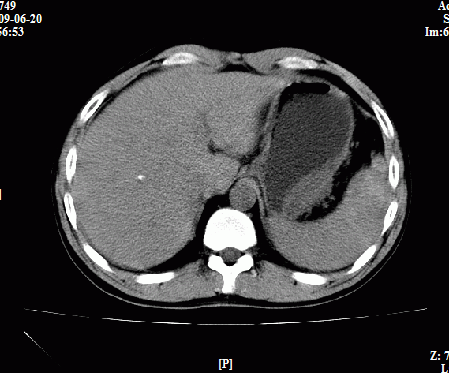

以下是引用随光逐影在2009-6-23 11:37:00的发言:[br]1)考虑胃癌;建议行胃镜检查进一步明确诊断。2)肝右叶肝内胆管结石(或钙化)。

以下是引用zxl51642在2009-6-23 11:31:00的发言:[br]胃大弯侧壁明显增厚呈软组织肿块,考虑胃癌可能性大,建议胃镜活检。